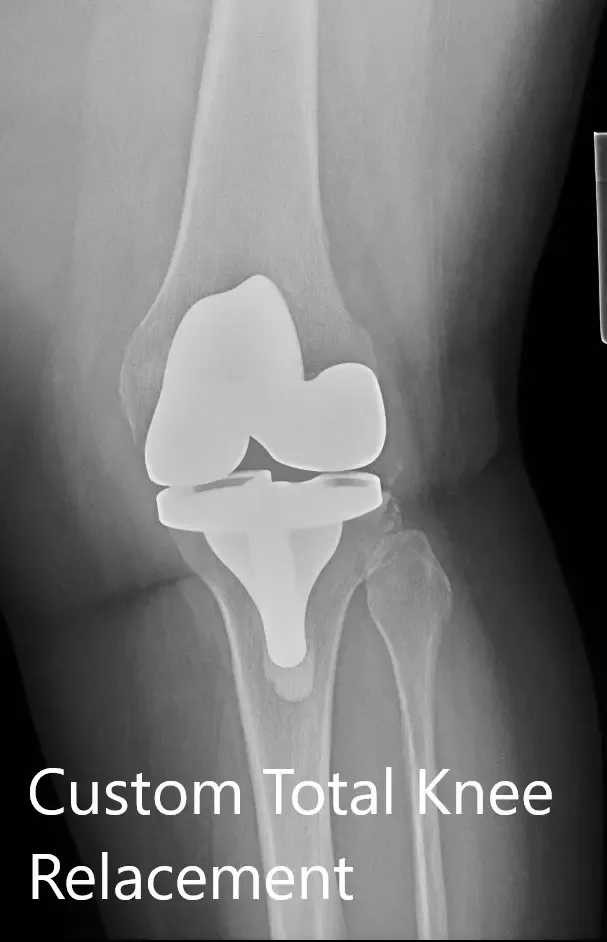

Postoperative X-ray showing the AP and lateral view of the left knee

IMPLANTS USED: Custom tibial tray with a custom femoral implant with 6-mm polyethylene insert with a patella of size 32-mm.